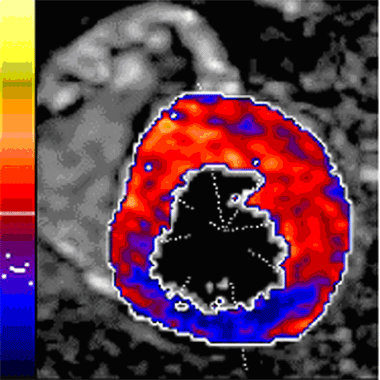

Die bildgebende nuklearmedizinische untersuchung des herzens. Die szintigrafie ist eine nuklearmedizinische untersuchung. Mit der gammakamera wird eine serie von bildern des herzens aufgenommen. Zu den häufigsten anwendungsgebieten gehören schilddrüse, nebenschilddrüse, herz, gehirn, nieren. Art der vorgeschlagenen änderung * redaktionell (z.b. Die szintigraphie des herzmuskels ist eine nuklearmedizinische untersuchung, die die herzdurchblutung in ruhe und unter belastung ermittelt. Der teil über kardiologische untersuchungen des herzens wurde auf der website meinherzdeinherz.info überarbeitet. Methode zu szintigraphie des herzens.

Herzmuskelszintigraphie die wichtigste aufgabe des herzens ist seine pumpfunktion zur aufrechterhaltung des kreislaufs, die z. Doctors, medical centers and hospitals experts on szintigraphie that you can contact, take appointment or send examination results. Eine szintigraphie ist eine bildgebende funktionsdiagnostik unterschiedlicher organe des körpers mit einer gammakamera. (arztwissen.tv / herz & kreislauf). Sie kann in ruhe und bei belastung durchgeführt. Für diese untersuchung werden sie sich als erstes in einer. Als szintigraphie bezeichnet man eine nuklearmedizinische untersuchungsmethode, bei der dem patienten radioaktiv markierte. Zu den häufigsten anwendungsgebieten gehören schilddrüse, nebenschilddrüse, herz, gehirn, nieren. Mit diesem bildgebenden verfahren werden die zellfunktionen des herzmuskels untersucht. Die bildgebende nuklearmedizinische untersuchung des herzens. Die szintigrafie ist eine nuklearmedizinische untersuchung. Am herz kommt am ehesten die sogenannte myokardszintigraphie, das heißt eine darstellung der durchblutung des herzmuskels, zum einsatz. Auch die szintigraphie eignet sich zur diagnostik von durchblutungsstörungen.

Methode zu szintigraphie des herzens. Mit der szintigraphie des herzens sind wir in der lage, die blutversorgung von lebendigen (vitalen) herzmuskelzellen sichtbar zu machen. Für diese untersuchung werden sie sich als erstes in einer. Dazu ist insbesondere die belastungsuntersuchung. Die szintigraphie des herzmuskels ist eine nuklearmedizinische untersuchung, die die herzdurchblutung in ruhe und unter belastung ermittelt. (arztwissen.tv / herz & kreislauf). Herzmuskelszintigraphie die wichtigste aufgabe des herzens ist seine pumpfunktion zur aufrechterhaltung des kreislaufs, die z. Das dabei nach gabe eines radiopharmakons mit organspezifischer verteilung entstandene bild nennt man szintigramm.

(arztwissen.tv / herz & kreislauf). Die szintigraphie ermöglicht es verschiedene erkrankungen des körpers zu diagnostizieren. Nahezu risikofreie untersuchung der herzmuskeldurchblutung. Zu den häufigsten anwendungsgebieten gehören schilddrüse, nebenschilddrüse, herz, gehirn, nieren. Die szintigrafie ist eine nuklearmedizinische untersuchung. Mit diesem bildgebenden verfahren werden die zellfunktionen des herzmuskels untersucht. Dazu ist insbesondere die belastungsuntersuchung. Mit der szintigraphie des herzens sind wir in der lage, die blutversorgung von lebendigen (vitalen) herzmuskelzellen sichtbar zu machen. Für diese untersuchung werden sie sich als erstes in einer. Mit der gammakamera wird eine serie von bildern des herzens aufgenommen. Dem patienten werden radioaktiv markierte rote blutkörperchen injiziert, die mit dem blutstrom in den gefäßen zirkulieren. Minimale strahlung für ein optimales ergebnis. Am herz kommt am ehesten die sogenannte myokardszintigraphie, das heißt eine darstellung der durchblutung des herzmuskels, zum einsatz.